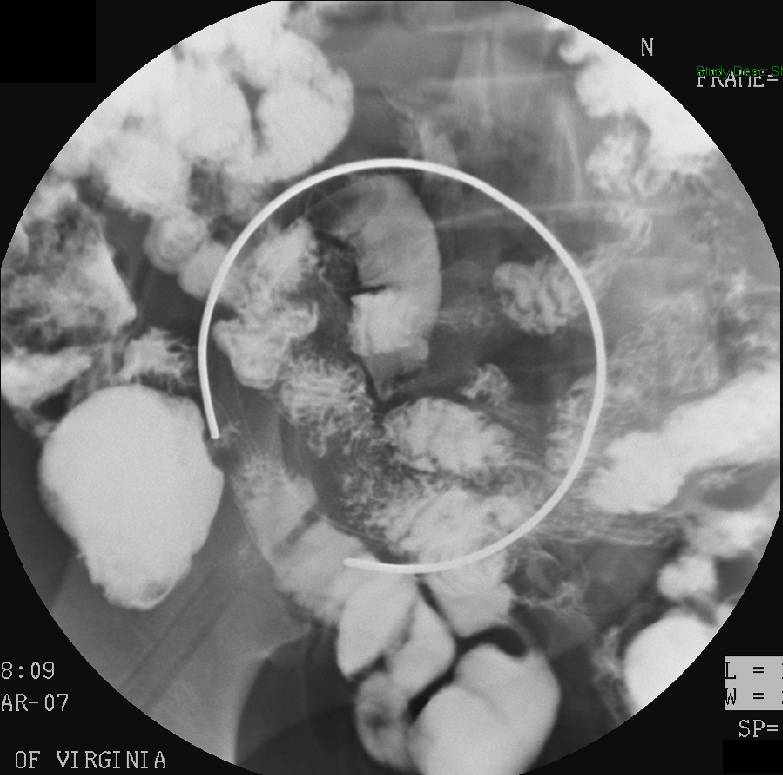

- Slide a compression paddle under the patient (balloon deflated) so that it is positioned on the duodenal bulb.

- There is a radiopaque ring on the paddle that will help you determine the center of the paddle.

- Inflate the bulb on the compression paddle and obtain single contrast compression spot films of the duodenal bulb and the C loop

(key image 14)

(key image 15)

(key image 16)

(key image 17)

(key image 18).

- Once the table is horizontal, obtain spot images of an air filled duodenal bulb. Placing the patient in a slightly steep left posterior oblique is usually best for obtaining these images.

(key image 22)

(key image 23)

(key image 24)

(key image 25)